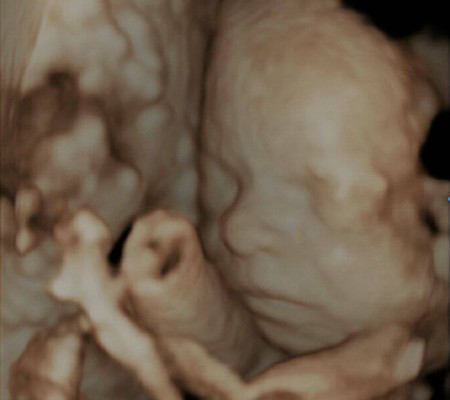

3D i 4D tehnologija omogućava da vidimo površinu bebe na lepši način i pokrete ploda u realnom vremenu.

Kao i 2D, 3D i 4D koriste ultrazvučni talas da se kreira slika bebe u materici. 3D je kreirana slika u prostoru dok 4D prikazuje pokret unutar materice pa možemo videti kako se beba smeje, mršti ili zeva.

Za prikaz ovih preseka potrebni su odgovarajući uslovi kao što su položaj ploda (lice ka nama), normalna količina plodove vode, poželjno je da ruke, noge i pupčanik ne budu ispred bebinog lica. U neodgovarajućim uslovima ovaj snimak nije moguće napraviti.